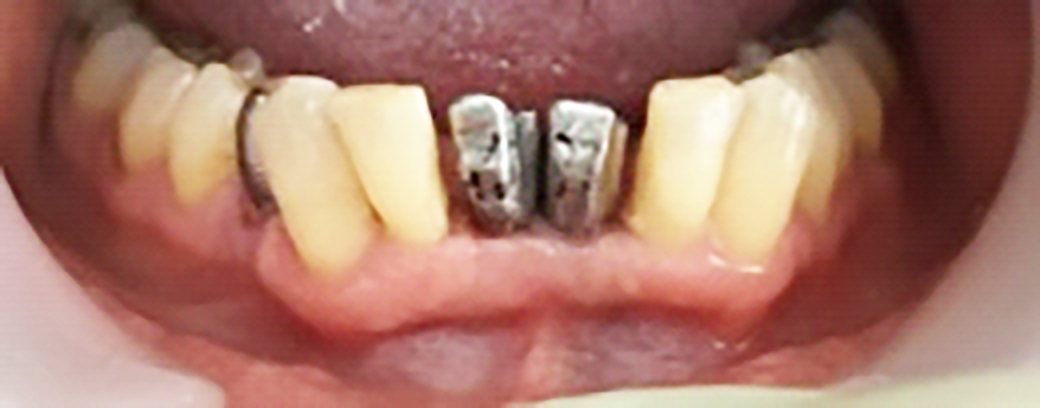

Si presenta alla nostra attenzione una paziente di 40 anni lamentando sensibilità, dolore alla masticazione e mobilità a carico degli incisivi centrali dell’arcata inferiore. Previa anamnesi medica e odontoiatrica si procede con l’esame obiettivo e con gli esami radiografici. Dall’esame obiettivo si osserva come gli elementi 3.1 e 4.1 risultino mobili, dalla radiografia si evidenzia un notevole riassorbimento osseo attorno agli elementi dentari in questione.

Previa anestesia locale si esegue lo scollamento di un lembo a spessore totale per consentire l’avulsione atraumatica degli elementi 3.1 e 4.1 (figure 1a-1b). Si revisionano le cavità alveolari e si posizionano osso bovino deproteinizzato e una membrana di collagene riassorbibile. Si sutura con filo 5/0, si posiziona un maryland bridge per garantire l’estetica in attesa dell’inserimento implantare e si esegue una radiografia di controllo (figure 2-4).